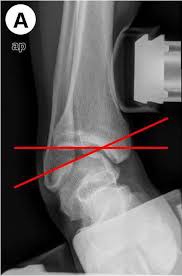

2. Stress X ray:照片子時,給脛骨內向外或前向後之力量,並在X光影像中,測量骨頭與骨頭的相對位移角度及長度,檢查個案是否為機械性損傷。

X 光

1. 承重下:比較兩邊腳踝是否對稱

(圖解) A圖: 固定遠端,並給脛骨一個向外的力量,使外側距腿關節面打開,測量其變化角度,正常應小於5度,大於9度或較好側多2倍的角度為不正常

(圖解) B圖: 固定遠端,並給脛骨一個向後的力量,使後側距腿關節面打開,測量其變化長度,正常應小於5mm,5-10mm或較好側多3mm為不正常